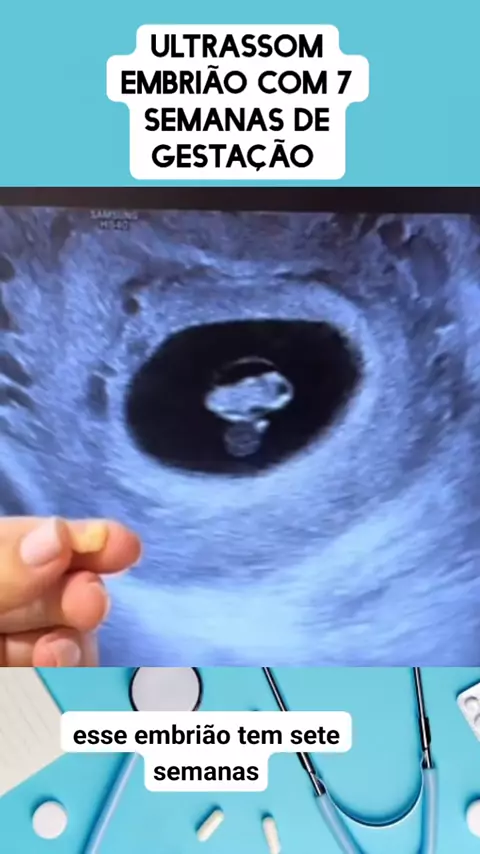

medicina em ação